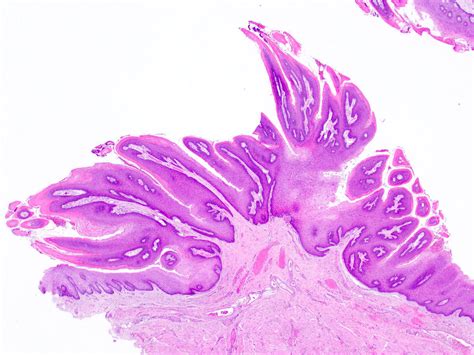

Discovering a small, wart-like growth inside your mouth can be an alarming experience, often triggering fears of serious disease. However, one of the most common benign lesions found in the oral cavity is the Oral Squamous Papilloma. This condition is essentially a localized proliferation of epithelial cells that results in a cauliflower-like or finger-like projection on the mucosal surface. Understanding what this lesion is, why it occurs, and when to seek medical advice is essential for maintaining oral health and peace of mind.

An Oral Squamous Papilloma is a benign, exophytic growth resulting from an infection caused by the Human Papillomavirus (HPV), most commonly types 6 and 11. Unlike malignant tumors, these papillomas are non-cancerous and do not have the potential to spread to other parts of the body (metastasize). They typically appear as solitary, painless, white-to-pink lesions with a roughened, pebbly surface.

Identifying an Oral Squamous Papilloma often involves observing its distinct morphology. Clinicians look for specific visual cues that differentiate this lesion from other oral pathologies like focal epithelial hyperplasia or squamous cell carcinoma. Because they are exophytic, they grow outward from the surface, often resembling a small cluster of grapes or a delicate cauliflower head.